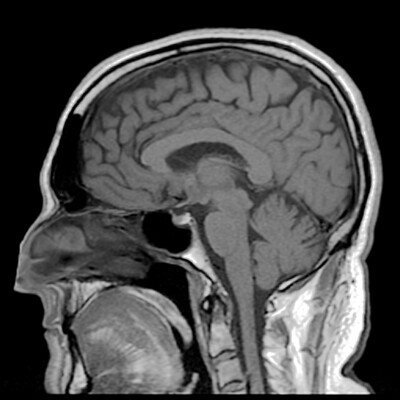

A detailed look inside the human brain

Scientists reveal the enormous complexity of a millimeter of the human brain